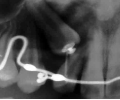

初診時